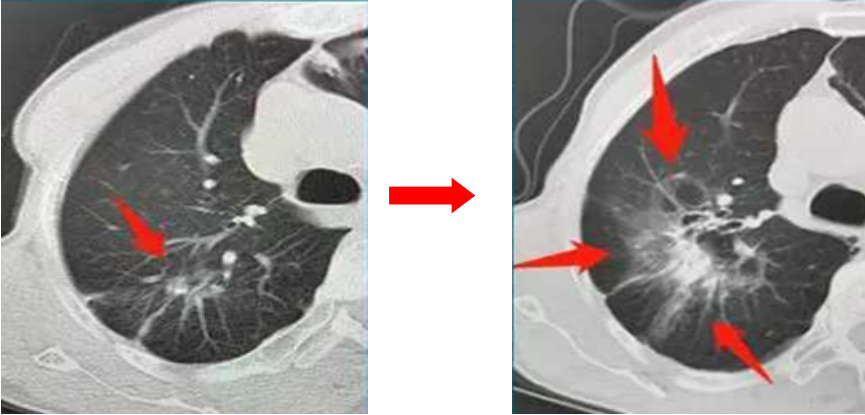

55歲的張先生兩年前查體發現了肺結節,認為自己既不抽煙,也不熬夜、酗酒,更沒有什么癥狀,應該沒什么事。醫生建議他每3個月復查一次CT,他置之不理,認為自己好端端的,干嘛還浪費那錢。結果兩年后出現咳嗽胸痛才想起來就診,發現原來5mm的肺結節已經長大了(見下圖),還出現了轉移,診斷為晚期肺癌,悔之晚矣。